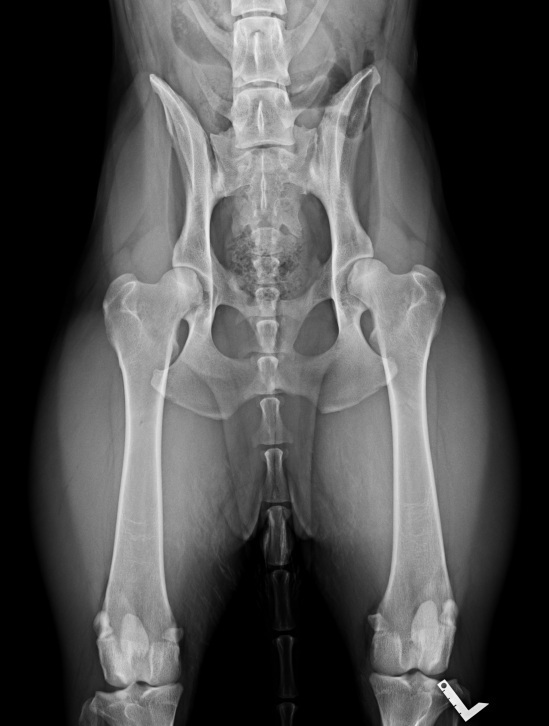

Radiographie des hanches d'un AS

La lecture des clichés permet de classer la dysplasie en cinq stades, de A (absence totale de dysplasie) à E (dysplasie sévère), en incluant les stades intermédiaires B, C et D.